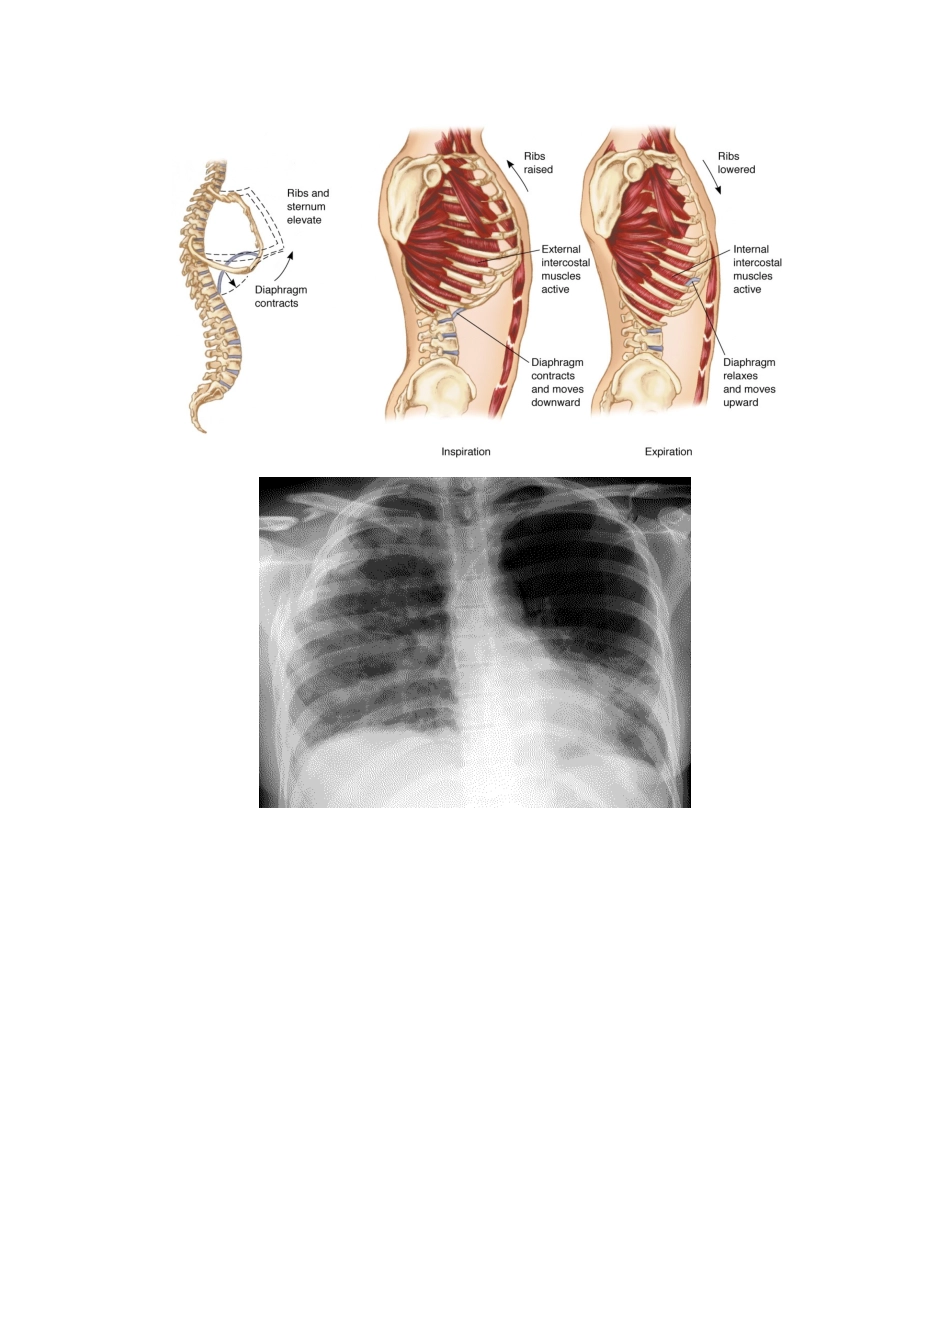

第二十六单元 胸部损伤考情分析202520252025合计ZY221ZL二十六、胸部损伤1.肋骨骨折(1) 解剖特点(2) 多根多段肋骨骨折(胸壁软化)的病理生理(3) 肋骨骨折的临床表现(4) 肋骨骨折的治疗方法2.损伤性气胸(1) 闭合性气胸的治疗(2) 开放性气胸的病理生理(3) 开放性气胸急救处理(4) 胸膜腔闭式引流的方法(5) 张力性气胸的临床表现(6) 张力性气胸的急救处理3.损伤性血胸(1) 血胸的来源(2) 损伤性血胸的病理生理(3) 进行性出血的判定4.心脏损伤心包压塞的临床表现和体征1.肋骨骨折暴力直接作用于肋骨,可使肋骨向内弯曲折断,前后挤压暴力使肋骨腋段向外弯曲折断。(1) 解剖特点:好发肋骨:4-7;中间四根,比较固定且靠外。相关知识: 第 l~3 肋骨粗短,且有锁骨、肩胛骨保护,不易发生骨折。 第 4~7 肋骨长而薄,最易折断。 第 8~1 0 肋前端肋软骨形成肋弓与胸骨相连,第 11~l 2 肋前端游离,弹性都较大,均不易骨折。好发年龄:成年和老年人;好发部位:直接暴力承力处、间接暴力向外折断、病理骨折协和习题.肋骨骨折最常见于A 1-3 肋B 4-7 肋C 8-10 肋D 11-12 肋E 肋弓答案;B(2)多根多处肋骨骨折(胸壁软化)的病理生理:记住——两个多多根多处肋骨骨折(包括两根两处)时有反常呼吸运动和纵隔扑动及病理生理改变。单根或数根肋骨单处骨折,其上、下有完整的肋骨支持胸廓,对呼吸功能的影响不大。多根多处骨折因前后端失去支撑,使该部胸廓软化,产生反常呼吸运动。多根多处肋骨骨折使局部胸壁失去完整肋骨支撑而软化,出现反常呼吸运动,即吸气时软化区胸壁内陷,呼气时外突,又称为连枷胸。 肋骨骨折断端可刺激肋间神经产生局部痛苦,在深呼吸、咳嗽或转动体位时加剧。 胸痛使呼吸变浅、咳嗽无力,呼吸道分泌物增多、潴留,易致肺不张和肺部感染。 胸壁可有畸形,局部明显压痛,挤压胸部痛苦加重,甚至产生骨摩擦音,即可与软组织挫伤鉴别。 骨折断端向内移位可刺破胸膜、肋间血管和肺组织,产生血胸、气胸、皮下气肿或咯血。 连枷胸常伴有广泛肺挫伤、挫伤区域的肺间质或肺泡水肿导致氧弥散障碍,出现低氧血症。胸部 x 线照片可显示肋骨骨折断裂线和断端错位,但前胸肋软骨骨折并不显示 x 线征象。【真题库】18.单侧多根多处肋骨骨折最严重的生理改变是(2025)A.痛苦,呼吸运动减弱B.胸壁软化,反常呼吸C.咳嗽,血痰D.严重皮下气肿E.出...